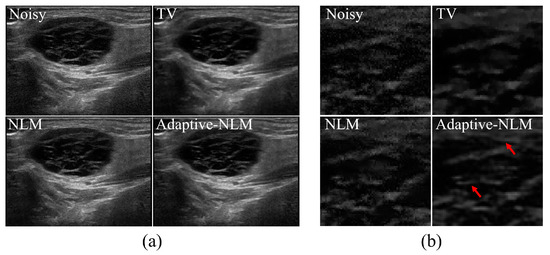

3. Results and Discussion